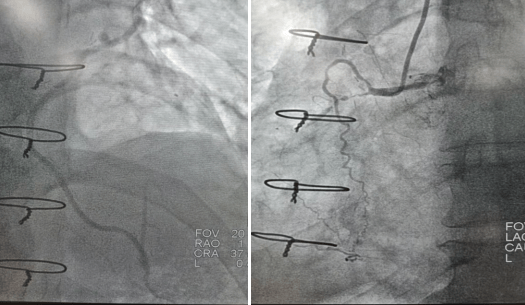

2022年9月16日行冠脉造影术,造影结果示:左主干末端99%狭窄,LAD近段100%闭塞,LCX开口及近段95%狭窄,乳内动脉-左前降支血管通畅,RCA近段100%闭塞,大隐静脉桥血管未见,考虑闭塞。

心血管病院吴栋梁院长、CCU李新国副主任、心血管内科二病区赵娟副主任、王端乐主治医师、宋睿主治医师介入团队造影后认真研究患者的病情和影像资料,决定开通闭塞长达11年的右冠状动脉,精确选择器械,选择同轴性及支撑力均好的指引导管,术中选用微导管辅助,软、硬导丝结合等技术,聚精会神、挥汗如雨,终于历经3小时的努力,成功前向开通右冠状动脉,精准选择由远及近“铺设”通过性较好、长度合适的支架 。

(术前术后对比)